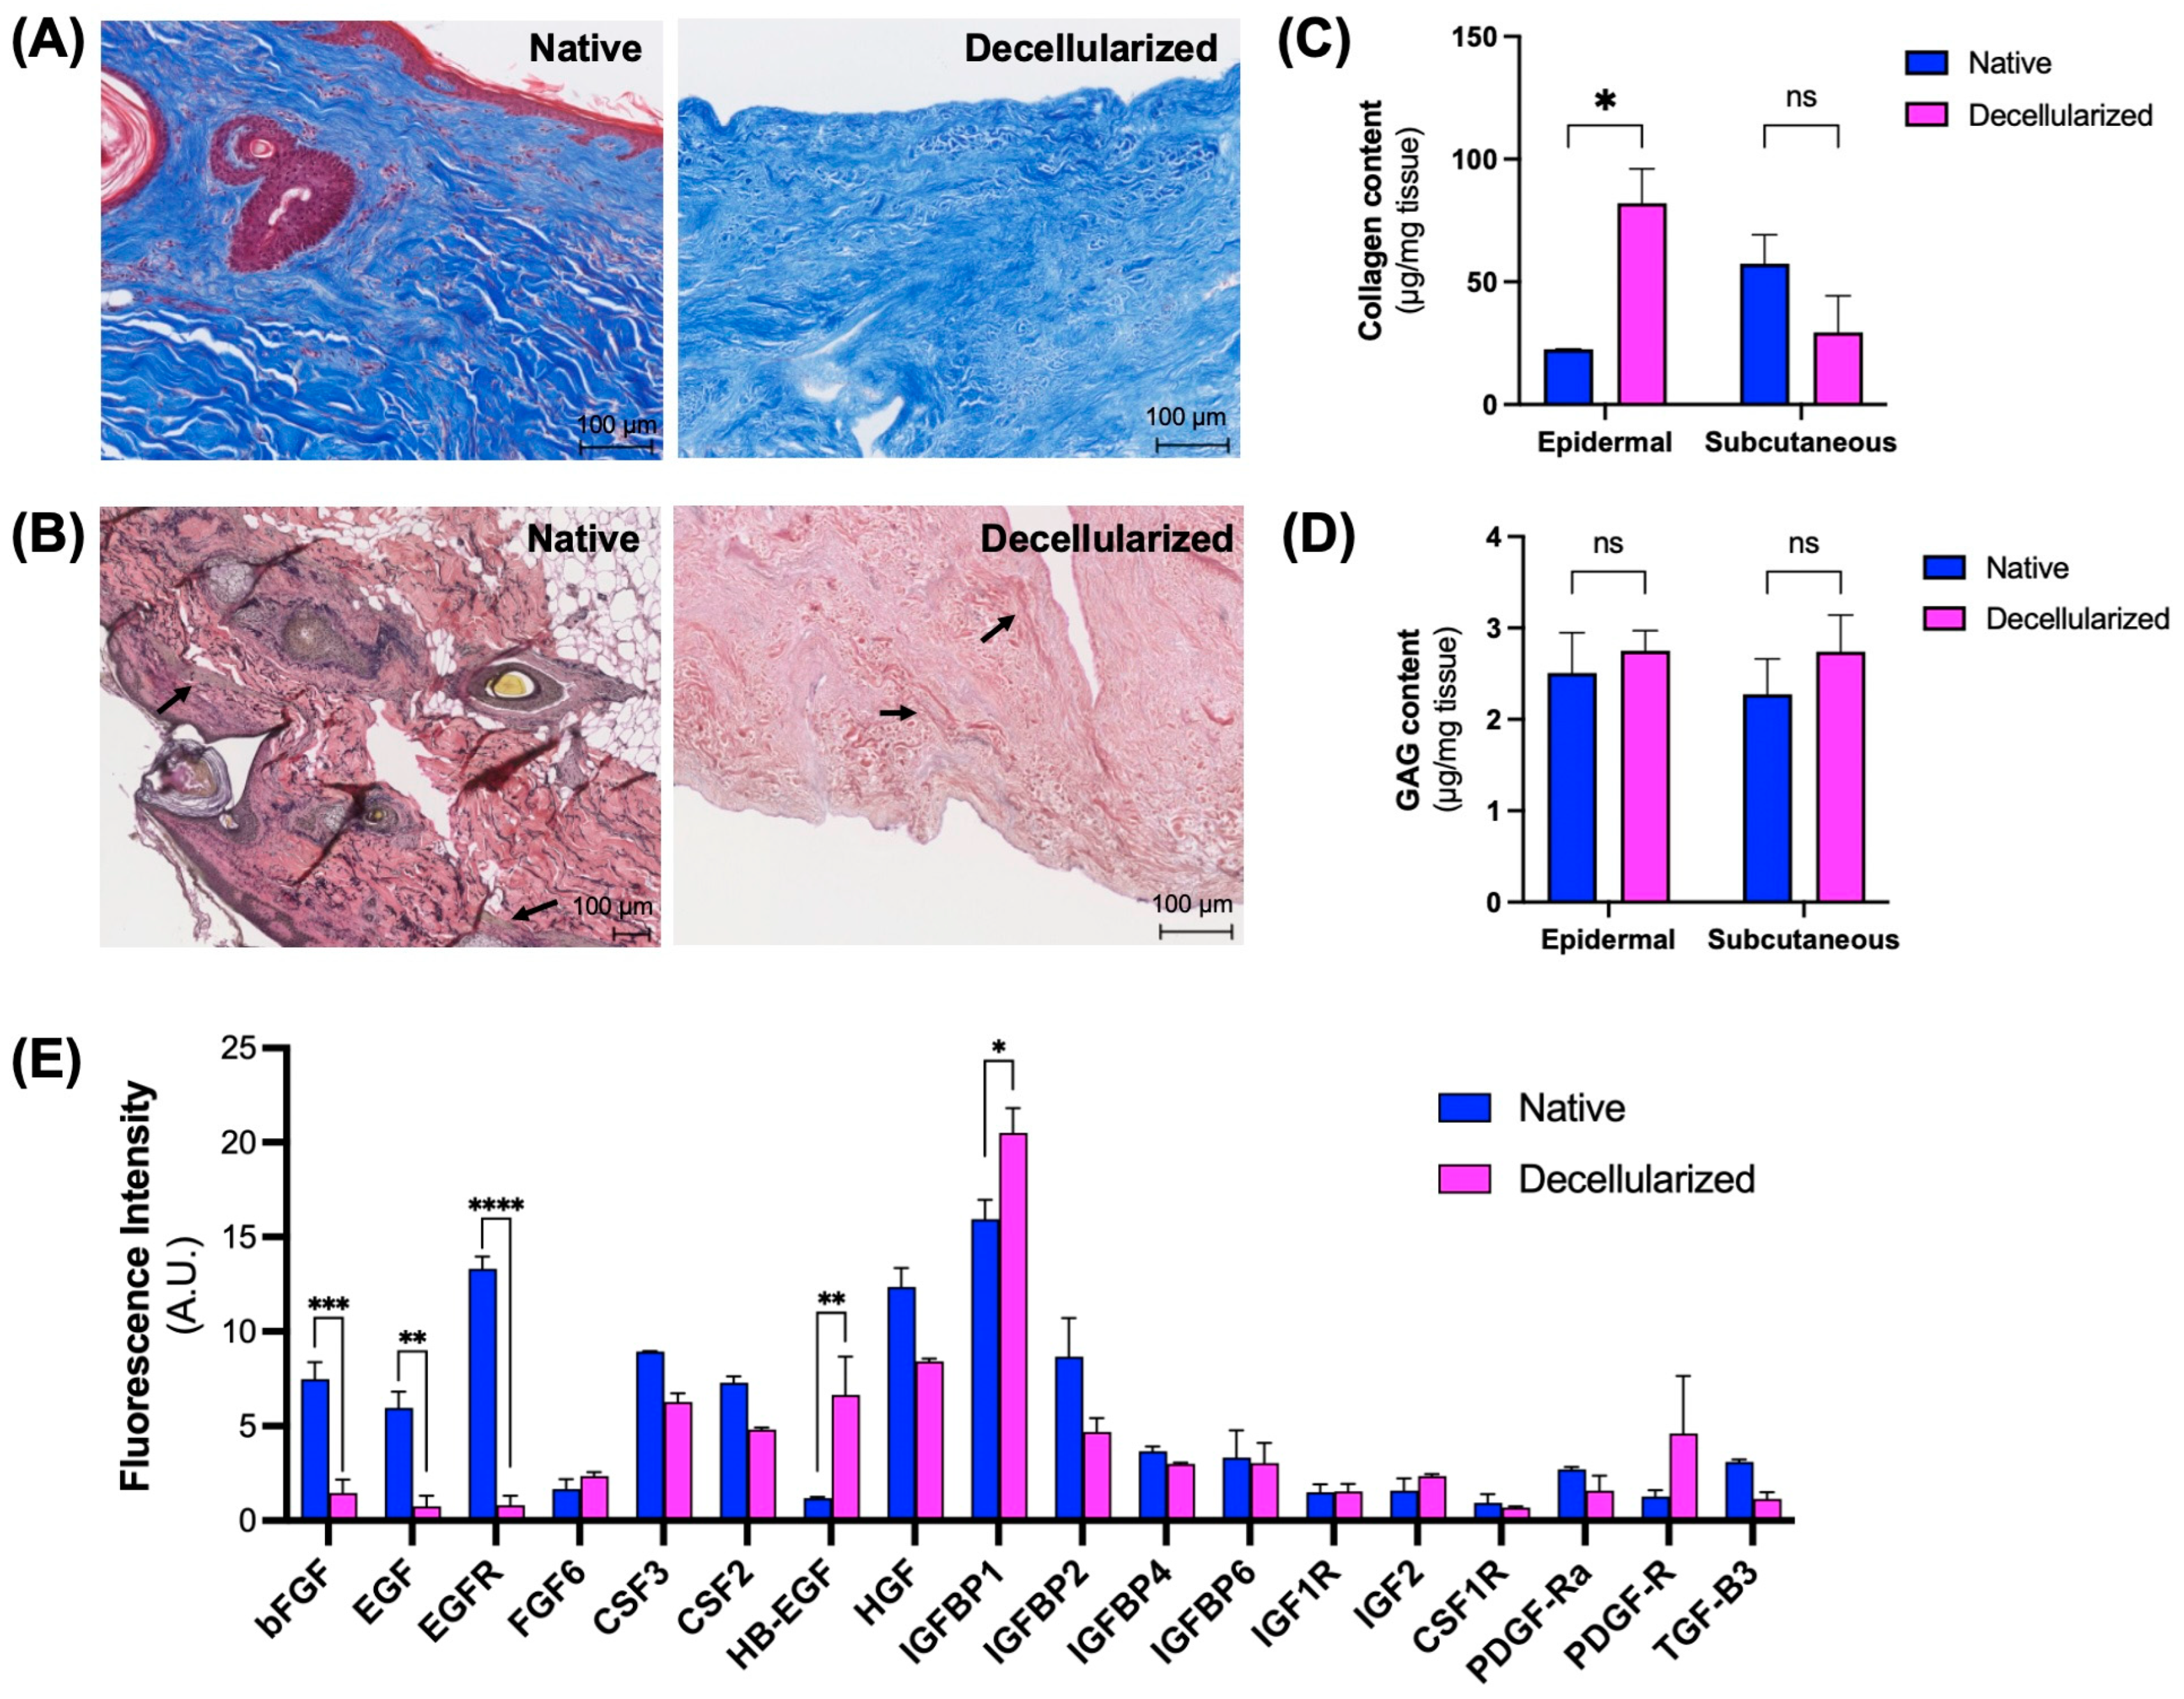

3.2. Maintenance of Extracellular Matrix (ECM) Components

3.3. Microarchitectural and Mechanical Characteristics of Decellularized Facial Grafts